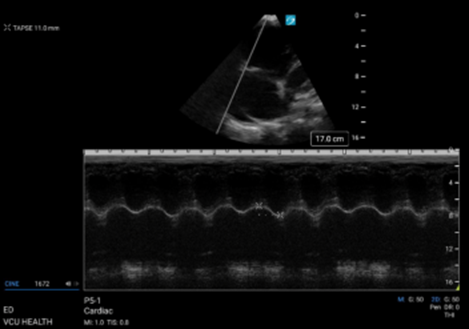

The second method for evaluating RV systolic function measures the distance or excursion, rather than velocity, of the lateral tricuspid annulus movement and is called tricuspid annular plane systolic excursion (TAPSE). To do this, an M-mode spike is placed through the lateral portion of the tricuspid valve in an A4C view, and a tracing is generated. (Figure 5) The TAPSE is measured from peak to trough of the resultant wave. The patient in this case had an abnormally low TAPSE of 11mm (normal values are greater than 17mm). Low TAPSEs have been associated with worse outcomes in the setting of acute PE.

Figure 5. M-mode tracing demonstrating an abnormally low TAPSE measurement.